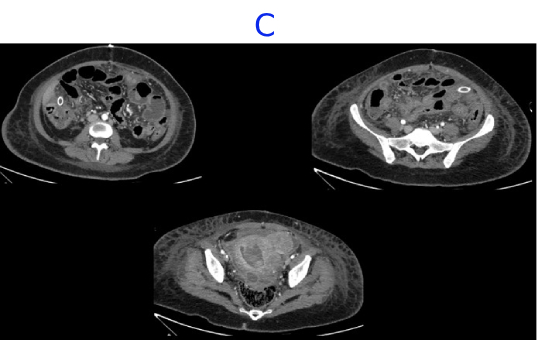

• C. CECT ABDOMEN AND PELVIS- DAY 7- STATUS POST EXPLORATORY LAPAROTOMY AND PERITONEAL LAVAGE

• D. Bulky uterus with a hypodense submucosal lesion protruding into the endometrial cavity from the fundus showing heterogeneous enhancement - infected vs infarcted fibroid. Abnormally enhancing endometrial lining with hypodense content within the endometrial cavity - possible endometritis with pyometra. Pelvic peritonitis with residual trace fluid in the pelvis. Interval resolution of pneumoperitoneum. Abdominal drains in situ.

• E. Bulky uterus with a hypodense submucosal lesion protruding into the endometrial cavity from the fundus showing heterogeneous enhancement - infected vs infarcted fibroid. Abnormally enhancing endometrial lining with hypodense content within the endometrial cavity - possible endometritis with pyometra. Left sided pyosalpinx.

• Bulky uterus with a hypodense submucosal lesion protruding into the endometrial cavity from the fundus showing heterogeneous enhancement - infected vs infarcted fibroid.

• Abnormally enhancing endometrial lining with hypodense content within the endometrial cavity - possible endometritis with pyometra

• Left sided hydro/pyosalpinx.